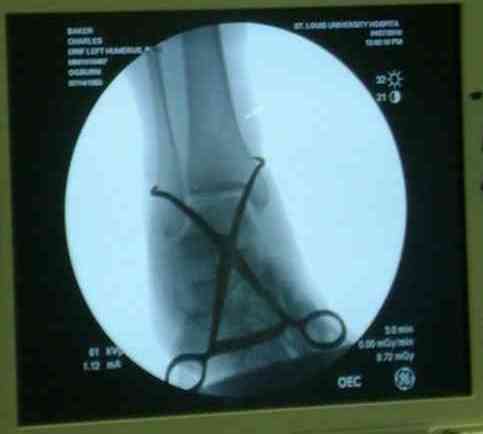

видели, все винты self tapping. Во втором случае у пациента с открытым многооскольчатым

переломом дистального плеча на 4 сутки выполнен остеосинтез. Обратите внимание =доступ без

резекции олекранона,медленная и ювелирная работа нетипичным для нас инструментом

закончена полным восстановлением анатомии локтевого сустава. В небольшой дефект залит

БМП\OP-1 Stryker ,продукт роста клеток человека в генной модификации\. Для профилактики

гетеротопической оссификации ряд врачей применяют облучение на 2-3 сутки.